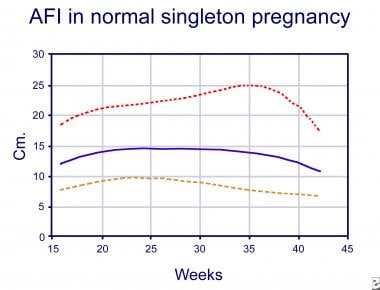

The ratio of amniotic fluid to fetal volume increases until about 30 weeks of gestation and then appears to decline.

During the first half of pregnancy, the amniotic fluid volume is closely correlated with fetal weight. After this point, the amniotic fluid volume declines at a rate of ~8% per week. The weekly volume increment then decreases and reaches zero at about 33 weeks of gestation at which point the mean AFV reaches its peak. finally decreases at 40 weeks to ~800 mLĪt 8 weeks the volume increases by ~10 mL/week, at 13 weeks the AFV increases by 25 mL/week and reaches a maximum rate of 60 mL/week at 21 weeks gestation.

The AFV undergoes characteristic changes with gestation. Pharmaceutical drugs are sometimes prescribed to treat polyhydramnios, such as indomethacin, but concerns have been raised over implications to the unborn baby and other side-effects.Physiology Change in volume through gestation If a fetal bladder obstruction is the cause of oligohydramnios, a small tube can be placed in the bladder to allow the fluid to flow into the amniotic sac. If the cause of the condition is known, then other treatmentsmay be applied. If needed, this option can be done more than once. The opposite is done in treatment of polyhydramnios, where a syringe is inserted into the amniotic sac to drain excess fluid. In some cases of oligohydramnios, extra fluid has been added to the mother's amniotic sac in an effort to increase amniotic fluid levels within the uterus. The amniotic fluid index chart shows the average volume of amniotic fluid in a pregnant woman based on gestational agein millimeter. There areseveral approachesto test the most commonly used methods are the four-quadrant techniqueand the 'single deepest pocket'. Unfortunately, effective treatments for polyhydramnios and oligohydramnios are limited. The amniotic fluid index (or AFI) is used to estimate the well-being of the fetus by doing an ultrasound of the uterus to estimate the levels of amniotic fluid levels in the uterus. Possible Treatments for Polyhydramnios and Oligohydramnios Polyhydramnios can also lead to certain congenital complications, including Down’s syndrome. Polyhydramnios can lead to many of the same complications as oligohydramnios, and the extra fluid can leak through the vagina in rare instances. The symptoms of polyhydramnios for this include edema, difficulty breathing, and excessive weight gain. There are often no symptoms experienced by the mother, except for their belly not growing in alignment with their duration of pregnancy, being smaller than it should. Having low levels of amniotic fluid inside the uterus during pregnancy can lead to numerous problems, which include miscarriage, premature birth, and stillbirth. With the amniotic fluid index chart above, you will wander what are the possible complications along with oligohydramnios and polyhydramnios? Low Amniotic Fluid Levels If there are high amounts of amniotic levels in a mother's uterus then it is known as polyhydramnios, whereas having small amounts of amniotic fluid can lead to oligohydramnios. What If I Have Abnormal Amniotic Fluid Levels? With the pregnancy process going on, the AFI values are changing, and the percentile for fetus age is usually referred as the cutoff value. The AFI 250mm is assumed as polyhydramnios. After 35 week, AFI levels usually begin to reduce. An average AFI level is 80 mm to 140 mm when you are in your 20 weeks to 35 weeks of pregnancy. Usually, the normal value of amniotic fluid index varies from 50 mm to 250 mm (or 5 cm to 25 cm). The sum of the four quadrants, in millimeters or centimeters, is amniotic fluid index. The deepest pocket without fetal parts or umbilical cord is then measured in millimeters or centimeters vertically. Using the umbilicus and the linea nigra as horizontal and vertical axis, an imaginary divide is created inside the uterus, which is split into four quadrants. Techniques and Values of Amniotic Fluid Index Charts Technique The amniotic fluid index chart shows the average volume of amniotic fluid in a pregnant woman based on gestational agein millimeter.Īmniotic Fluid Index Chart Percentile Values